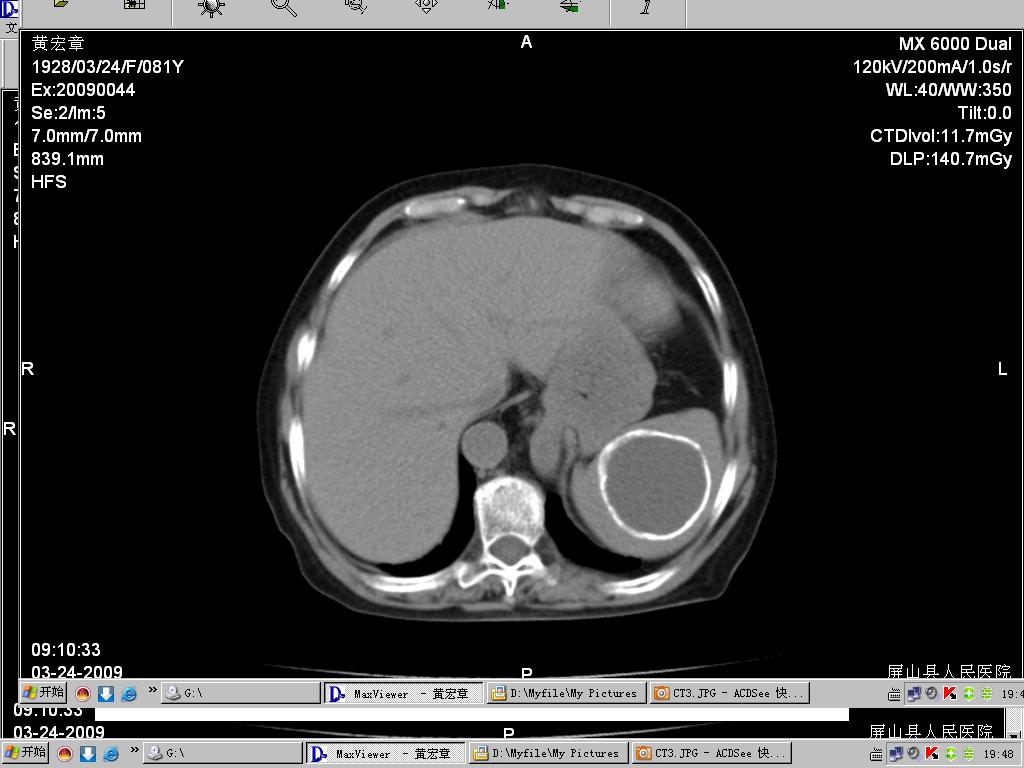

病人女,81岁,临床以呕血为主诉!请大家帮忙分析!

1、ct征象:脾实质内可见一类圆形囊性病变,其壁呈连续完囊钙化,病变内密度均一,病变与正常脾实质界限清楚。

2、诊断:首先考虑脾内良性囊性占位,包虫可能性大,不完全排外脾囊肿。(包虫囊肿壁钙化机率相对高,而单纯囊肿壁可以钙化,而完全钙化的少见)。

脾脏囊肿是脾脏组织的囊性病变,可分为寄生虫囊肿和非寄生虫囊肿;寄生虫囊肿常见包虫病,“囊中囊”是其特征性改变,常与肝包虫病并发,此例病灶内密度均匀,肝脏内无病灶也不符合。

非寄生虫囊肿大多为脾外伤后血肿退变的结果,也可见于脾梗死后ct表现单发或多发圆形、类圆形低密度影,境界清楚,壁菲薄,偶尔可伴有钙化,增强扫描无强化。形成过程是外伤引起脾脏的血肿,血肿被包裹,血液被吸收,周围形成纤维性囊壁,囊液不断蓄积,逐渐形成浆液性孤立性囊肿,囊肿可以很大,囊壁无内皮细胞被覆,其内常含血液,一般可追逐到外伤史,晚期可发生钙化。本例最为符合。